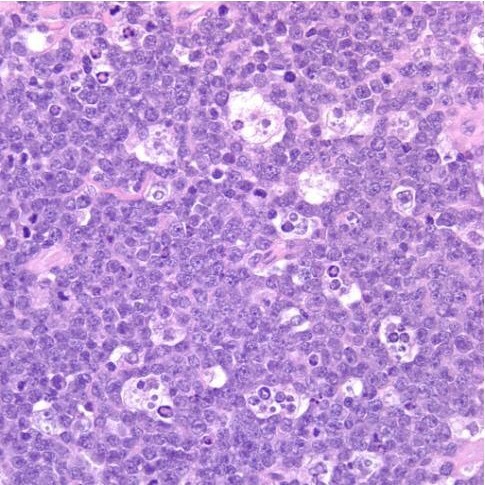

What are two major differentials to consider if you saw this biopsy image?

What does this image show?